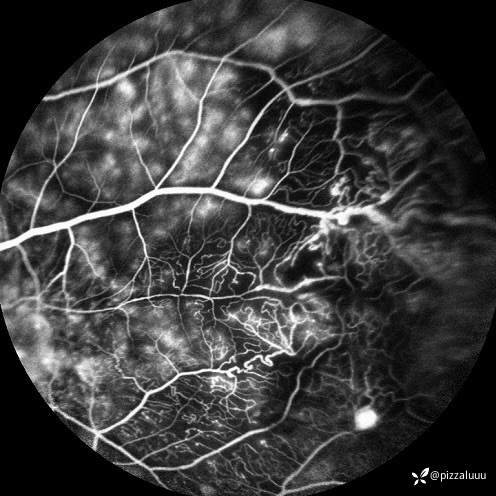

今天补充了FFA、AF和眼底照相。很典型的coats,后极部视网膜可见块状不规则而隆起的黄色渗出。AF可见病灶处低自发荧光。FFA所见:视网膜毛细血管扩张迂曲及异常血管形态,以小动脉明显,管壁呈囊样扩张,有梭形、串珠样动脉瘤。大片无灌注区。异常血管早期渗漏明显,形成强荧光斑,晚期荧光融合。由于大片黄白色渗出位于外丛状层,对视网膜血管荧光影响不大。可看到脉络膜背景荧光遮蔽。